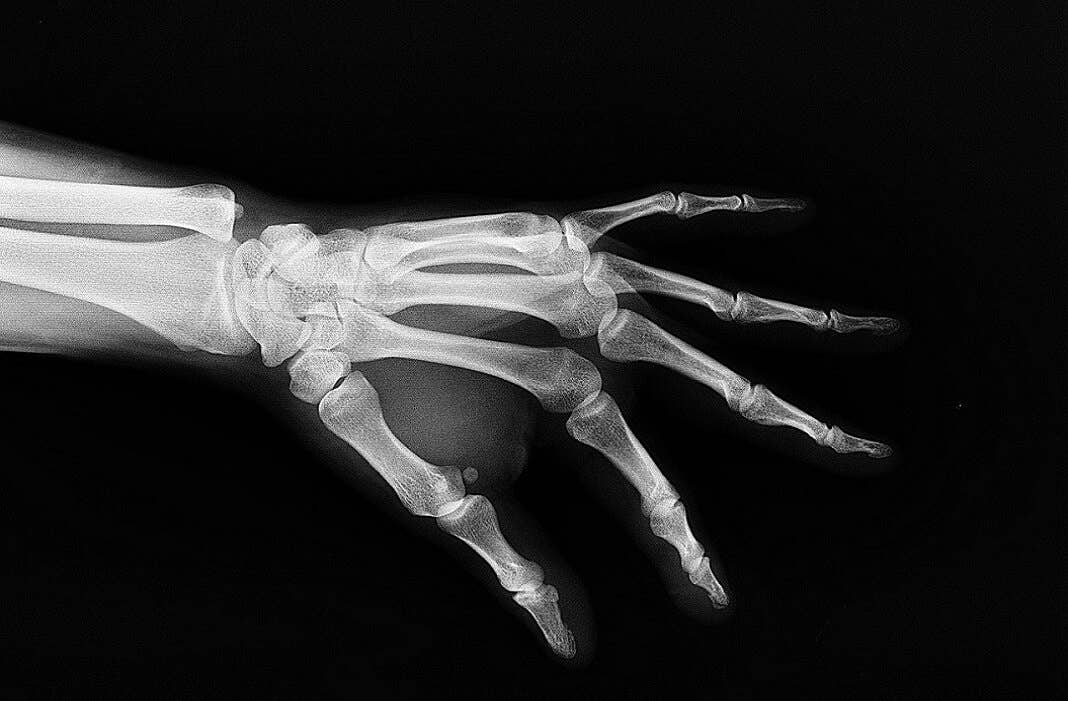

It may sound far-fetched, but for patients needing reconstructive surgery, this could soon be the pitch from Danish startup Particle3D. The company is pioneering a novel method for 3D printing lightweight, customized bone implants that fuse with your skeleton before slowly disappearing.

Particle3D’s process most often starts with scans of a patient’s bones or the area where the implant will be placed. The data is fed into a computer program, which allows surgeons and staff to optimize the implant design using CAD computer models. A customized implant is then printed by Particle3D and sent to a hospital for insertion.

3D printing TCP enables the company to create more porous implants. The porous structures allow the implants to function as scaffolds for blood vessels and natural bone to grow, and the implants degrade over time as they are supplanted by natural bone. Trials on pigs and mice have shown new bone marrow and blood vessels developing in the implants after as little as eight weeks.